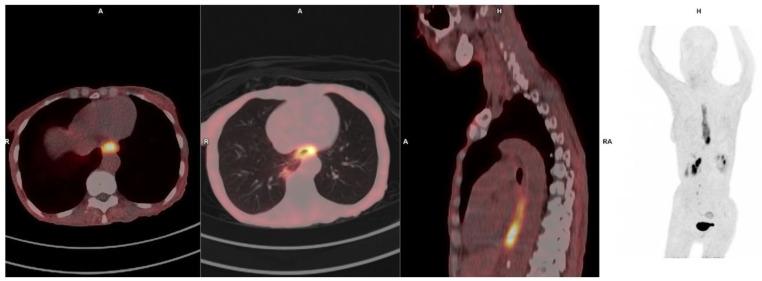

Fibroblast activation protein (FAP) is a serine protease selectively expressed in cancer-associated fibroblasts (CAFs), fibrotic tissues, and areas of active tissue remodeling, making it an attractive target for diagnostic imaging across a spectrum of disease. FAP inhibitors (FAPIs) labeled with PET tracers have rapidly advanced as a novel imaging modality with broad clinical applications that offers several advantages, including rapid tumor accumulation, low background uptake, and high tumor-to-background ratios. In oncology, FAPI PET has demonstrated excellent performance in visualizing a wide range of malignancies, including those with low glycolytic activity, such as pancreatic cancer, cholangiocarcinoma, and certain sarcomas. Its high sensitivity and specificity for the stromal component enables improved tumor delineation, staging, and response assessment. Additionally, the potential to guide theranostic approaches, where the same tracer can be labeled with therapeutic radionuclides, positions FAPI as a key player in precision oncology. Beyond oncology, FAPI PET has shown promise in imaging conditions characterized by fibrotic and inflammatory processes. In the cardiovascular field, FAPI PET imaging is being investigated for its ability to detect myocardial fibrosis and active cardiac remodeling, crucial in conditions like heart failure, post-myocardial infarction remodeling, and hypertrophic cardiomyopathy. This review highlights the expanding clinical applications of FAPI-based PET imaging across oncology, inflammation, and cardiovascular disease. While the current data are promising, further large-scale studies and multicenter trials are essential to validate these findings and establish standardized protocols. The versatility and broad applicability of FAPI PET underscore its potential as a transformative tool in precision medicine.

成纤维细胞活化蛋白(FAP)是一种丝氨酸蛋白酶,在癌症相关成纤维细胞(CAF)、纤维化组织和活跃的组织重塑区域中选择性表达,这使其成为一系列疾病诊断成像的有吸引力的靶点。用PET示踪剂标记的FAP抑制剂(FAPI)作为一种具有广泛临床应用的新型成像方式迅速发展,具有多种优势,包括肿瘤快速聚集、低本底摄取和高肿瘤与本底比值。在肿瘤学中,FAPI PET在可视化多种恶性肿瘤方面表现出色,包括那些糖酵解活性低的肿瘤,如胰腺癌、胆管癌和某些肉瘤。其对基质成分的高敏感性和特异性有助于改善肿瘤的勾勒、分期和反应评估。此外,由于可以用治疗性放射性核素标记相同的示踪剂,FAPI在指导治疗诊断方法方面具有潜力,使其成为精准肿瘤学的关键参与者。除肿瘤学外,FAPI PET在以纤维化和炎症过程为特征的成像条件下也显示出前景。在心血管领域,正在研究FAPI PET成像检测心肌纤维化和活跃心脏重塑的能力,这在心力衰竭、心肌梗死后重塑和肥厚型心肌病等疾病中至关重要。本综述强调了基于FAPI的PET成像在肿瘤学、炎症和心血管疾病中的临床应用不断扩大。虽然目前的数据很有前景,但进一步的大规模研究和多中心试验对于验证这些发现并建立标准化方案至关重要。FAPI PET的多功能性和广泛适用性突显了其作为精准医学中变革性工具的潜力。